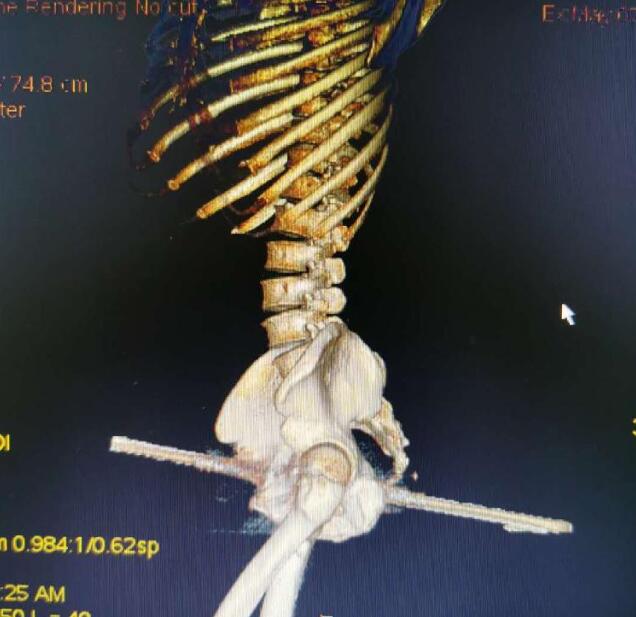

到達醫院后,消防員們被醫院工作人員帶到手術室外,按要求換好衣服后進入手術室,“當時看見一名男子側躺在手術臺上,一根鋼筋從臀部穿過男子身體! 天文特勤站隊長助理耿家家說,據他目測,臀部那一側鋼筋裸露在外有20厘米長,另一側裸露在外10厘米左右,鋼筋直徑在1.5厘米左右。后經測量,鋼筋長度在45厘米左右。

據介紹,因為鋼筋已經穿過男子身體,取出鋼筋需要將多余的部分切斷。而切斷鋼筋有兩種方案,一是用無齒鋸鋸斷,但是會產生火花,也有一定的導熱性,可能會燒傷皮膚。第二種方案是用荷馬特剪切鉗將鋼筋剪斷。

據了解,被鋼筋刺穿身體的男子44歲,當天在工地作業時,不小心從1米多高的地方摔落,被地上豎立的鋼筋從右臀部向前側貫穿。

“雖然鋼筋刺穿了身體,但幸運的是避開了血管、坐骨神經、股動脈等重要位置!敝貞c市東南醫院骨科副主任譚云說,經過前期治療患者的生命體征比較穩定,院方經過會診提出兩種方案,一是將右臀部表面組織全部切開,露出鋼筋。另一中方案就是將鋼筋從身體內抽出。

“考慮到第一種方案對患者損傷較大,決定采取第二種方案!弊T云說,雖然鋼筋在工地已經被截斷,但還是留下不少,并且鋼筋為螺紋鋼,如果按正常的方式抽出,會帶出部分體內組織,對患者造成更大的傷害,為了最大限度減少患者損傷,也方便操作,決定求助消防用專業工具剪切。